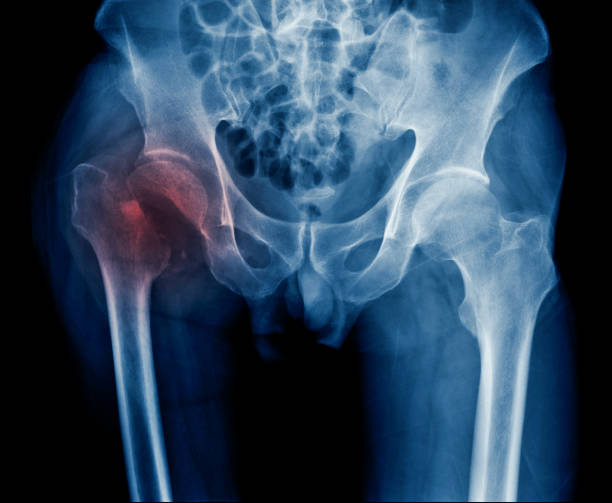

고관절 충돌 증후군

고관절 충돌 증후군은 엉덩이 통증의 주요한 원인 중 하나입니다. 이 질환은 골반 뼈와 대퇴골 사이에서 발생하는 충돌에 의해 2 관절 사이의 연골이 손상되는 질환입니다. 고관절의 구조적인 문제나 잘못된 자세, 과도한 스트레칭 등으로 발생할 수 있습니다.

관절염

엉덩이 관절의 염증이나 변형으로 인해 엉덩이 통증이 발생할 수 있습니다. 나이가 들어가면서 관절염이 악화되어 엉덩이 통증이 생기는 경우가 많습니다. 이러한 경우에는 전문의의 치료와 적절한 관리가 필요합니다.